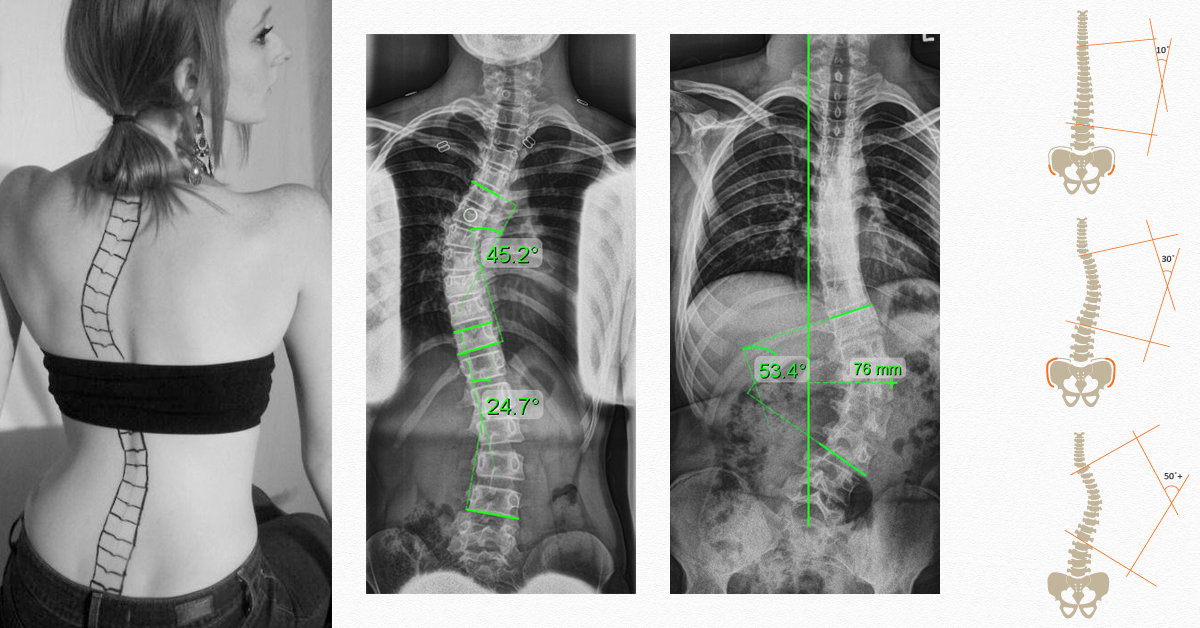

ภาวะโรคกระดูกสันหลังคด สามารถรักษาให้กลับมาใกล้เคียงภาวะปกติได้ หากได้รับการรักษาโดยถูกวิธีและในเวลาที่เหมาะสม

- นำ MRI หรือ ฟิมล์ X-Ray มาตามนัด (หากมี) หลังตรวจประเมินและทราบโปรแกรมที่เหมาะกับการรักษาโรคกระดูกสันหลังคดของตนเอง สามารถสอบถามค่าใช้จ่ายที่หน้าเคาร์เตอร์ได้โดยตรง